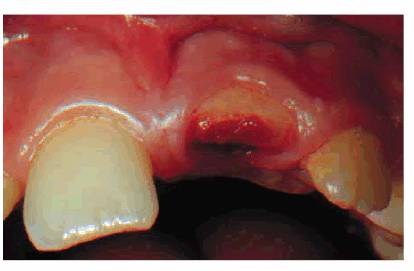

periodontal therapy because of pain in a maxillary central incisor tooth (Figures 19-38A, and 19-38B). The combined dental procedures

have created stress on the pulpal complex that have exceeded the pulp's ability

Figure 19-38A: Maxillary central incisor with a chronically inflamed (stressed) pulp.

Figure 19-38B: A histologic section of chronic inflammation, irreversible pulpitis, with round cell infiltration. (Photograph courtesy of Dr. Harold R. Stanley.)